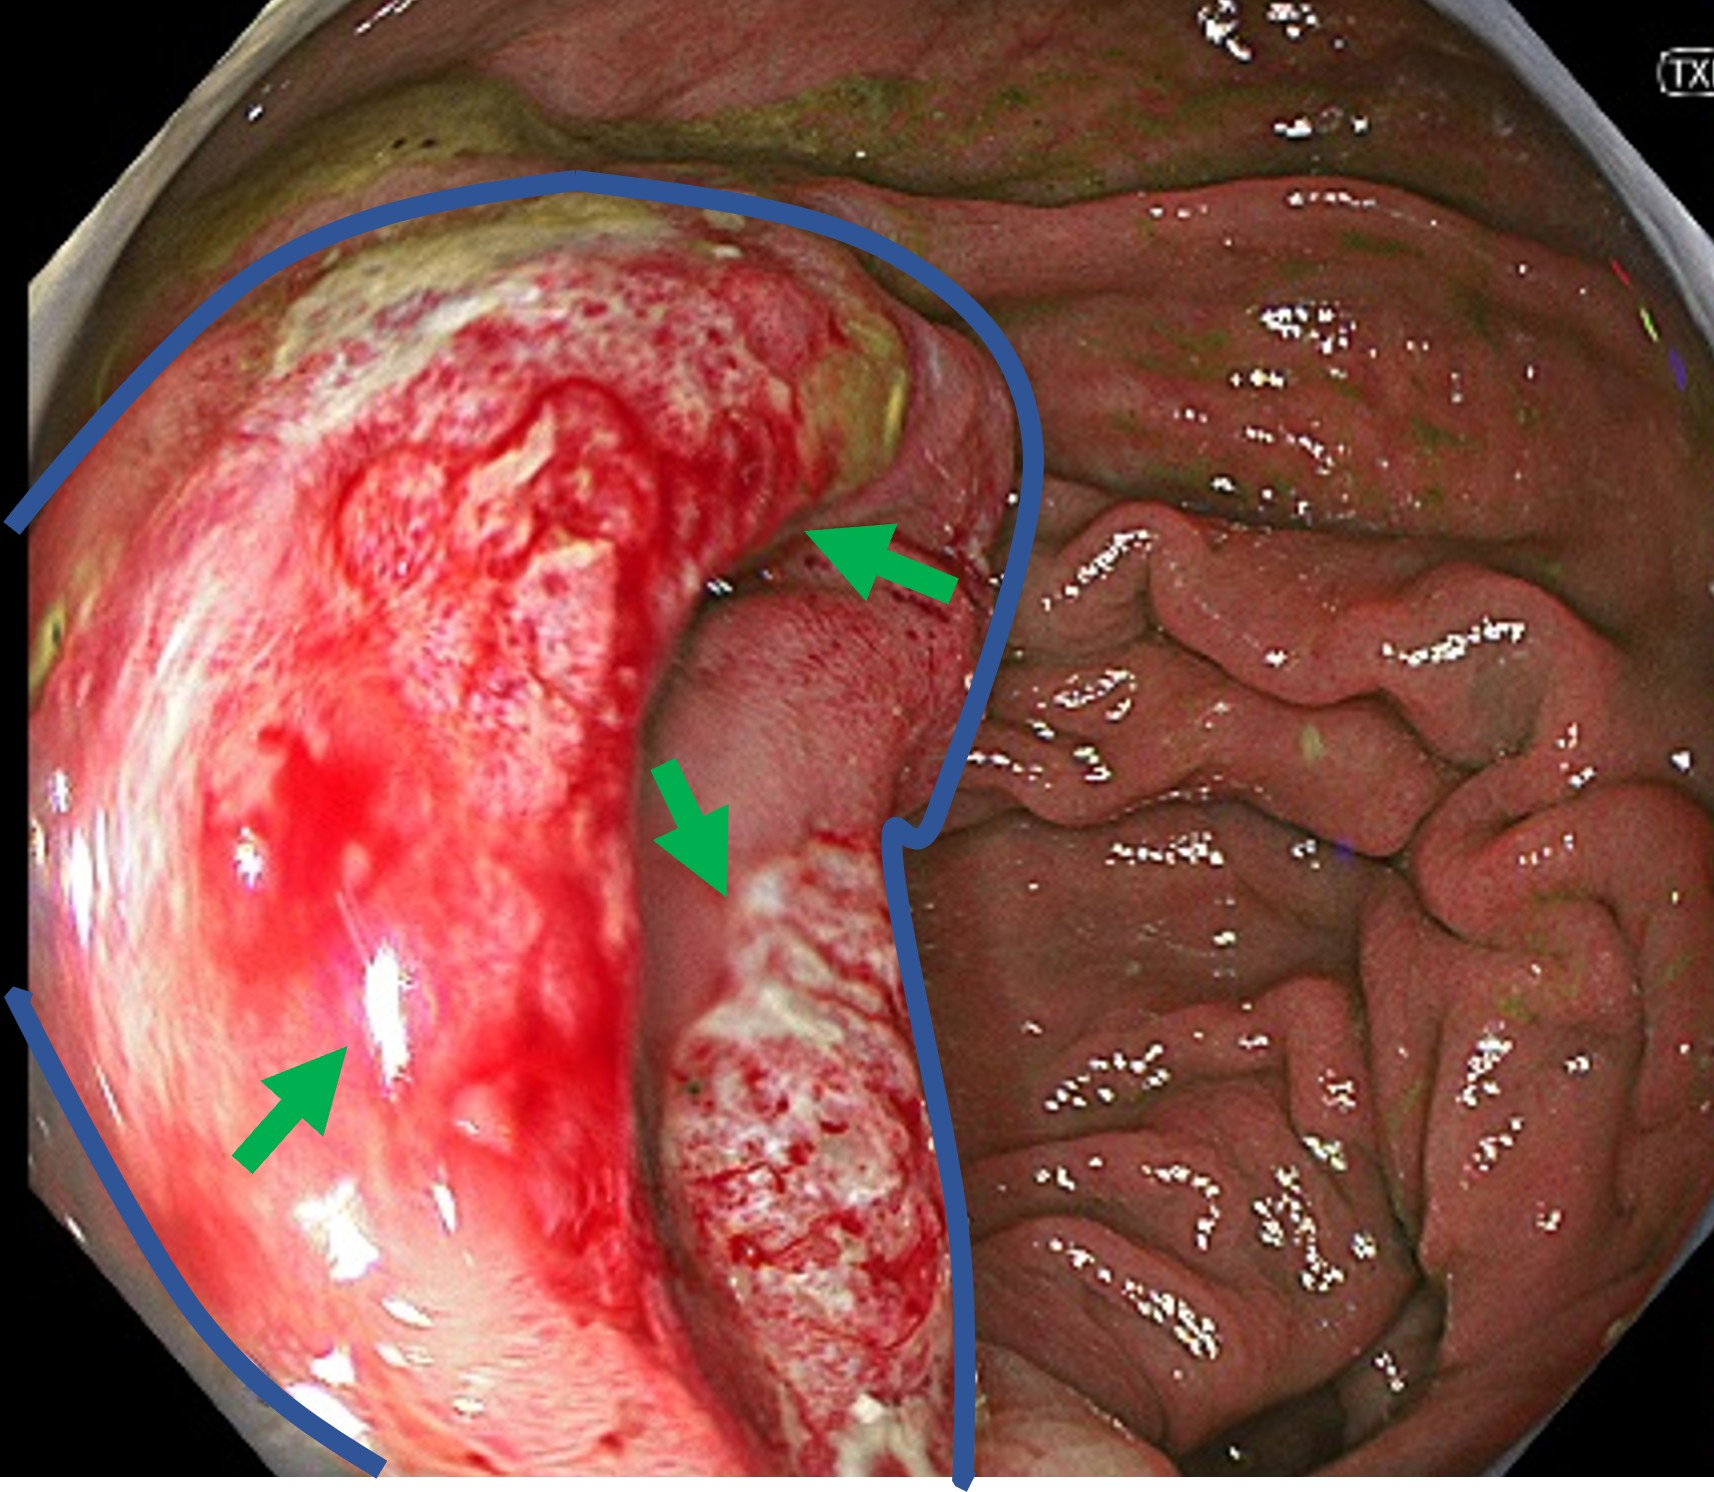

大腸内にまだらなびらん・発赤を認め、特に最深部の大腸と小腸のつなぎ目(バウヒン弁)に強い炎症を認めました。

内視鏡所見からはカンピロバクターと呼ばれる細菌の感染を強く疑う所見で、この部位からの細菌培養検査でカンピロバクター菌も検出され、カンピロバクター腸炎と診断しました。

実際の大腸カメラの画像です。大腸と小腸のつなぎ目のバウヒン弁と呼ばれる部分(青線で囲まれた部分)に出血やびらんなどの炎症を認めました(緑矢印)